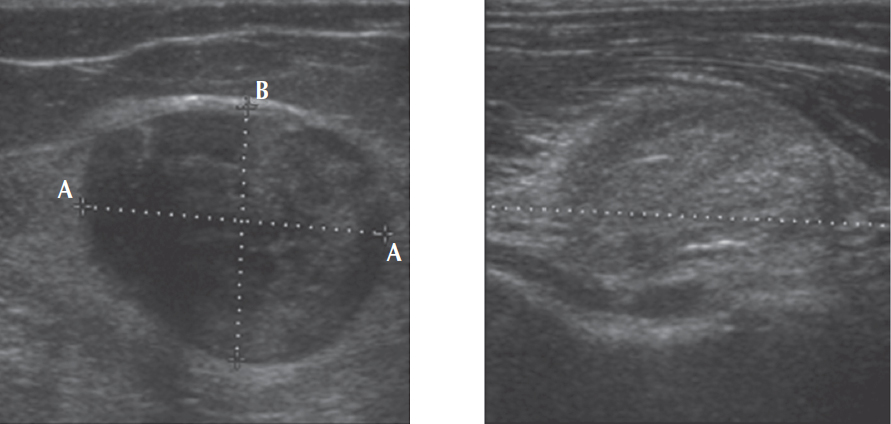

Ультразвуковое изображение опухоли нервного ствола — это обычно анэхогенное образование, не всегда однородной эхогенности. С учетом особенностей анатомического строения опухоли и ее расположения внутри нервного ствола опухоль будет иметь округлую или овальную форму с ровными контурами и четкими границами. Иногда можно визуализировать веретенообразную форму, при которой видно распространение опухоли по нервному стволу. Использование режима цветового дуплексного картирования позволяет выявить наличие собственных сосудов опухоли, а также определить взаимоотношение пораженного нерва с рядом лежащими магистральными сосудами. Если при эхолокации наблюдают нечеткие границы опухоли, инвазивность взаимоотношений с окружающими тканями и сосудами, то можно предположить злокачественный характер новообразования (рис. 1) [16, 17].

Рис. 1. УЗИ объемного образования локтевого нерва

Fig. 1. Ultrasonographic visualisation of ulnar nerve sheath tumour